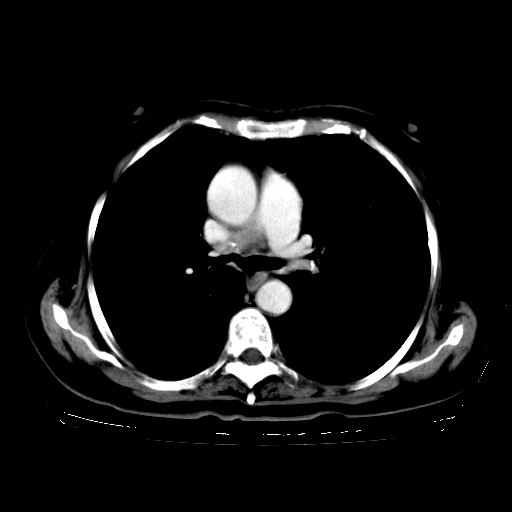

女,70岁,咳嗽、咳痰一个月,低热一周。

1.左上肺结核,部分纤维化。右肺中下叶部分肺不张,内见液化、坏死及点状钙化,右中下叶支气管壁增厚、管腔狭窄,见多个点状钙化,结合临床考虑支气管内膜结核,建议痰检查抗酸杆菌并参考血沉。两肺多个小圆点状高密度灶,境界模糊,多考虑结核肺内播散。但本人年龄较大首先应支气管镜检以除外右肺癌。

2.胸主动脉夹层。

一元论:内膜结核伴下肺阻塞性肺炎并双肺播散!另:主动脉夹层。右侧少量胸腔积液。

继发型肺结核,右下肺支气管内膜结核.右侧少量胸腔积液.主动脉夹层.

支气管内膜结核肺内播散.右侧少量胸腔积液.主动脉夹层.